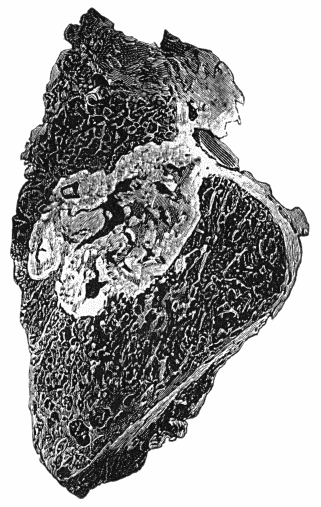

118.Shaft of the Femur after Acute Osteomyelitis 444

119.Femur and Tibia showing results of Acute Osteomyelitis 445